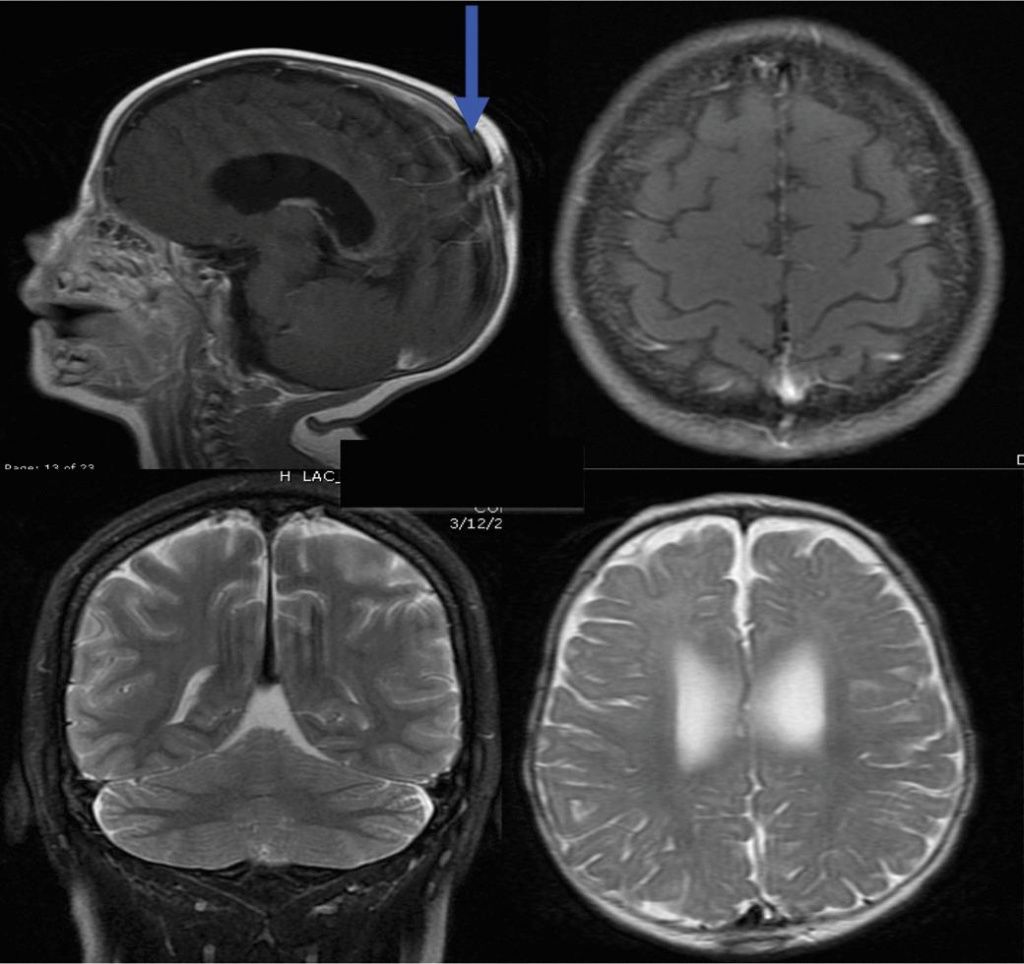

Демиелинизирующие заболевания мозга: МРТ изображения